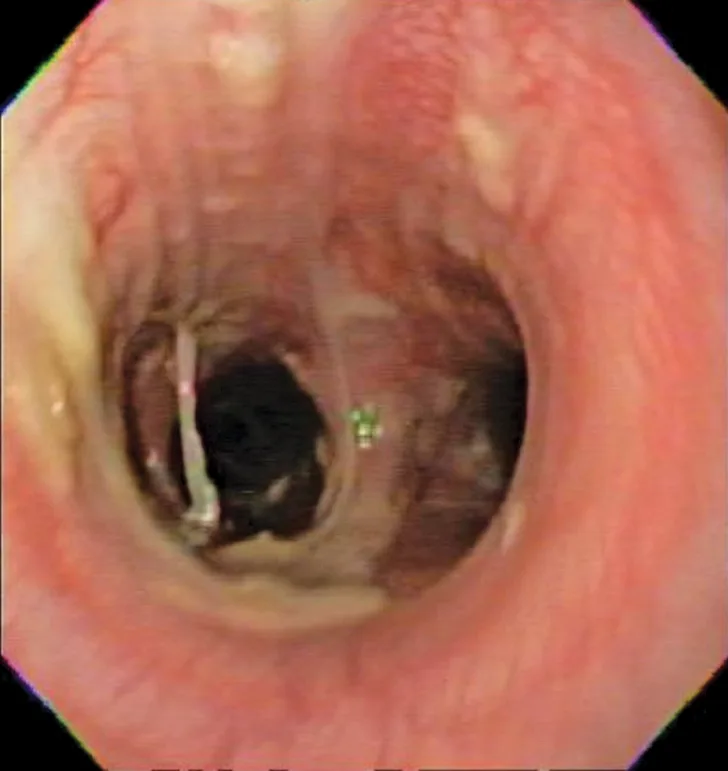

Bronchoscopy results demonstrating mucosal irregularity, hyperemia, and characteristic greenish-yellow airway exudate

Bronchoscopic visualization revealed a moderate amount of thick, adherent, greenish-yellow mucus in the trachea and secondary and tertiary bronchi; mucosa was moderately irregular and erythematous (Figure 2). There was no evidence of airway collapse. Samples were collected via bronchoalveolar lavage for cytology, aerobic culture, and Mycoplasma spp culture.

Cytologic evaluation of the airways confirms eosinophilic inflammation, which is the hallmark of diagnosis. The percentage of eosinophils (mean, 61% of the total nucleated cell population4) exceeds that of healthy dogs (5%-24%).2,5,10 Samples can be obtained via tracheal wash or bronchoscopy. Bronchoscopy allows for visualization of more characteristic airway associated changes (eg, greenish-yellow secretions, irregular mucosa, hyperemia).2,5,11 Occasionally, intraluminal granulomas may be present,4 allowing for mucosal brush samples or biopsies that can further support a diagnosis. Tracheal washes provide appropriate cytologic samples in most cases. Bronchoscopy is generally reserved for patients with more focal radiographic disease, concerns for neoplasia, or suspicion for concurrent structural disorders (eg, bronchial collapse, tracheal collapse).